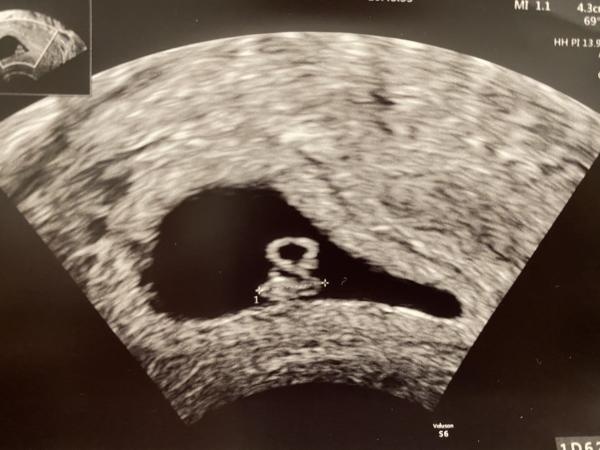

Idag gjorde jag ultraljud, hjärtat pickade och beräknas vara vecka 6+5 :) så bf 8/8, samma datum som med vårat minsta barn haha!